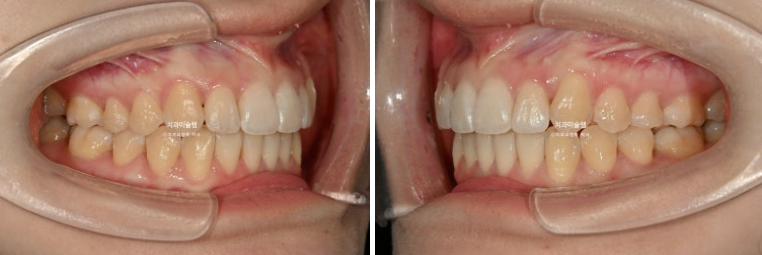

25.01~25.11

고무줄을 열심히 껴준 탓에 좌측 교홥관계는 좀 더 1급에 가까워졌습니다.

우측은 완벽한 1급을 달성했습니다